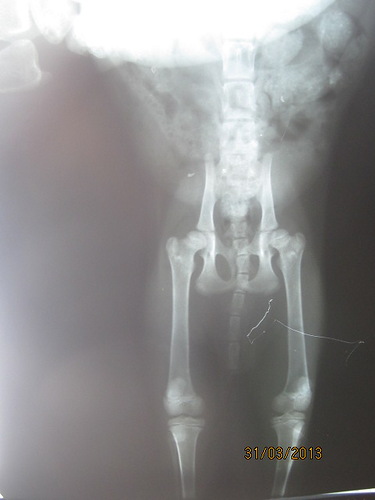

Отсутствие лучевой кости на лапах!!! Кости вообще НЕТ!!!

Шипучка писал(а):СЕЙЧАС ЗАГРУЖУ все. правда плохо видно-солнце слепило в окно(

во вторник со снимками поедим к хирургу-получим назначения-пока только Циклофирончик сказали поколоть и в ушках клеща немного.